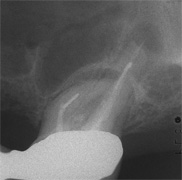

Dieser Zahn wurde schon geraume Zeit zuvor von einer Kollegin im Notdienst eröffnet und anschlies­send mit einer aufwendigen Amal­gamrestauration ästhetisch an­sprechend wieder verschlossen. (Bild 1) Uns blieb noch WK/WF, was bei massiver Überstopfung der hin­teren Wurzel auch gelang (Bild 2).

"Überstopfen ist immer noch besser als Unterstopfen" laut Koçkapan. OK, hier wurde des Guten aber ganz eindeutig zuviel getan.

Also direkt neben dem Zahn das Zahnfleisch ein wenig angehoben und zur Seite gedrängt und dann mit einem scharfen Löffel den Überschuss vollständig entfernt.

Schon 8 Monate später ist eine deutliche Verbesserung der Gesamt­situation unverkennbar (Bild 3). Verlorengegangene Knochensubstanz wurde in Teilen schon wieder aufge­baut, doch ist noch gar nichts entschieden. Schaun mer also ma'.

Abrechnungstechnisch hat der Mut zur WR an 38 gefehlt, deshalb nur EXZ1.